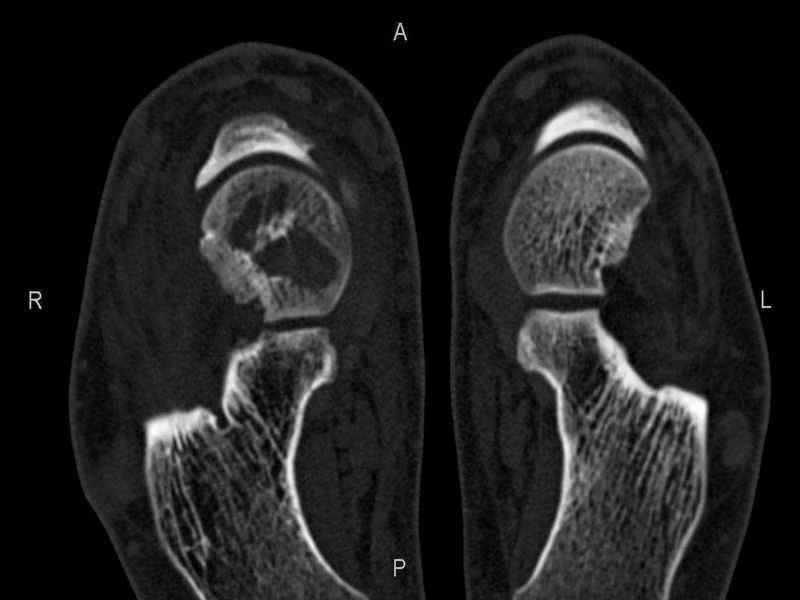

Уважаемые коллеги, обратился за помощью пациент, мужчина, 25 лет. С жалобами на болевой синдром в области голеностопного сустава и среднем отделе стопы. Травму отрицает. Со слов, болевой синдром в течении 1 года. Последние 1-1.5 мес периодически вынужден пользоваться костылями. После ограничения нагрузки боли уменьшаются.Соматически здоров. До появления болей активно занимался рукопашным боем. На СКТ картина рассекающего остеохондрита блока таранной кости, киста шейки таранной кости с признаками импрессии суставной поверхности. А также - разрастания переднего края б\берцовой кости сопровождающиеся клиникой импиджмент синдрома. Предполагаемый план лечения- удаление свободного фрагмента суставного хряща из трансмаллеолярного доступа с рассверливанием поверхности дефекта, кюретаж кисты шейки с заполнением полости биокомпозитом + дебридмент переднего отдела голеностопного сустава. Прошу высказать своё мнение, за и против, предполагаемого плана лечения. А также по возможности ответить на вопросы: 1. Есть ли необходимость в улучшении васкуляризации таранной кости (например подтаранный артродез). 2. Учитывая планируемое применение биокомпозитного цемента целесообразно ли заполнение им дефекта блока таранной кости с моделированием края суставной поверхности.

СТ чётко демонстрирует секвестр, но открыв сустав вероятно, что хрящ тарана окажется интактным и только пальпацией/ ЭОП можно будет

идентифицировать локализацию секвестра. Если вы с этим столкнетесь, то секвестрэктомию я бы предложил сделать не со стороны суставной поверхности тарана, а со стороны угла тарана, субхондрально кюрретаж стенок, разнонаправленную туннелизацию спицей или 1.1мм сверлом и заполнить дефект спонгиозным графтом.